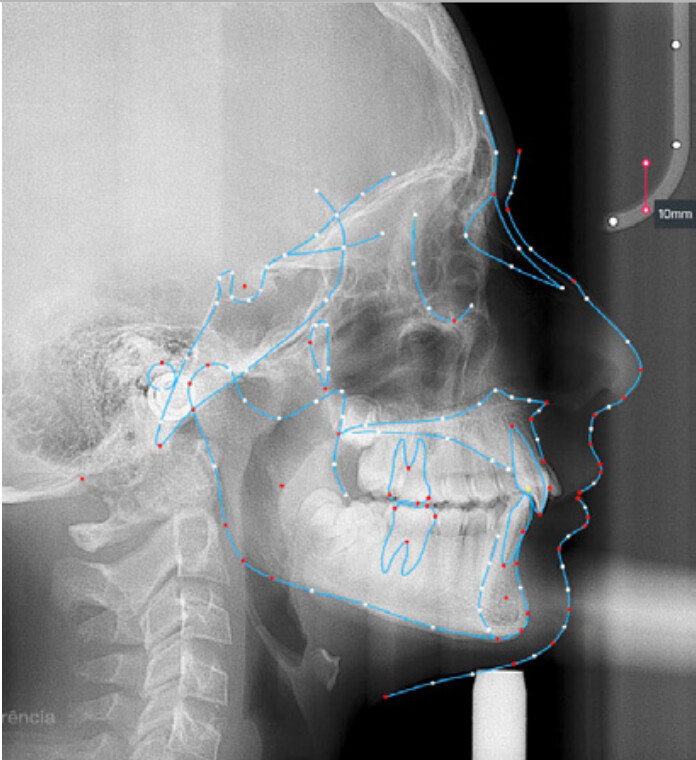

Um paciente do sexo masculino, com 13 anos de idade, apresentou-se com uma mordida profunda, caracterizada pela cobertura quase completa dos incisivos mandibulares. A avaliação clínica revelou apinhamento em ambas as arcadas, rotações dentárias e proclinação dos incisivos laterais superiores, contribuindo para as preocupações estéticas do paciente. O perfil facial era retrusivo, consistente com retrognatismo mandibular, e não foram detectadas anomalias periodontais significativas.

DIAGNÓSTICO:

O paciente apresentava uma relação esquelética de Classe II com molares e caninos bilaterais em Classe II e um padrão dentário de Classe II divisão 2. A mordida profunda estava associada a um apinhamento anteroinferior e a uma curva de Spee acentuada. A análise facial revelou boa simetria, um terço facial inferior ligeiramente aumentado e um perfil convexo caracterizado por retrusão mandibular e do mento. A competência labial estava ligeiramente reduzida, com diminuição do ângulo nasolabial e leve tensão do músculo mentoniano, fatores que comprometiam a harmonia facial global.